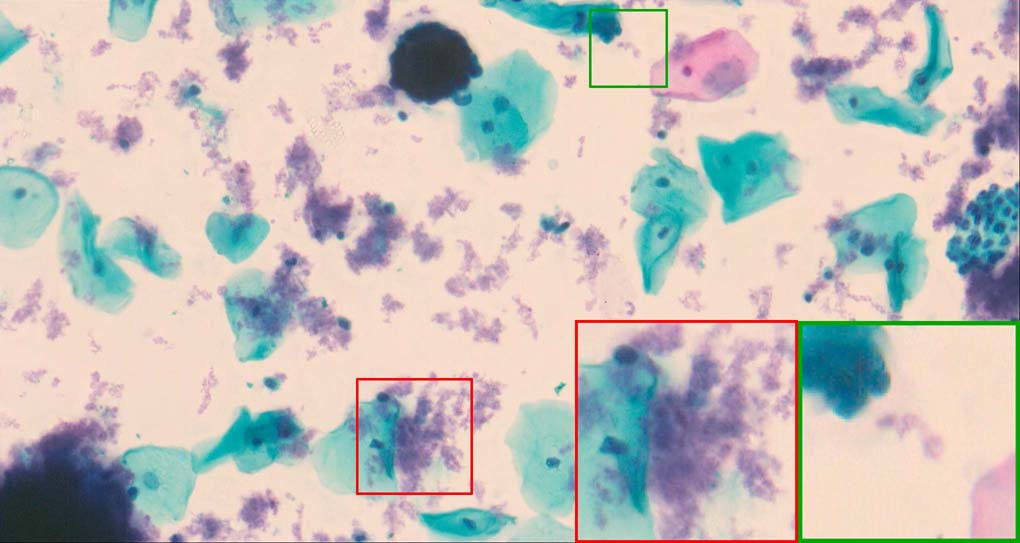

A good image fusion method should contain the following properties. First, it preserves both the details of small size objects and the integrity information of large size objects in the fused image, even in the case of the size of the interested objects varying largely in the image. For example, the cervical cell images from the microscope contain both small size isolated cells and large size agglomerates, which are both useful for cervical cytology [5]. Second, it should be efficient enough to handle large-scale data. For instance, it needs to process thousands of fields of view (FoV) in an acceptable time for the whole slide scanning in digital cytopathology [6], which requires to fuse a series of high resolution images captured at each FoV in a very efficient way. Third, it does not produce obvious artifacts. Despite being studied extensively, to our best knowledge, existing fusion methods may not meet these requirements simultaneously.

To demonstrate the effectiveness and efficiency of the proposed image fusion method , we conduct a set of comparative experiments on three image datasets. The first is composed by 8 pairs of multi-modal medical images and the second one contains 15 pairs of multi-focus gray or color natural images. These two datasets are often used in many related papers and some examples are shown in Figure 3(a) and Figure 3(b). The third one is a new multi-focus cervical cell image dataset collected by ourselves, which consists of 15 groups of color images and each group contains a series of multi-focus cervix cell images with size of or , etc. Some source examples are shown in Figure 3(c). Our source code implemented in C++ along with the new multi-focus cervical cell image dataset is available online.

Figure 9, Figure 10 and Figure 11 show the comparative fused results of the multi-focus cell images shown in Figure 3(c). For clarity, we also present a closeup view in the right-bottom of each sub-picture in Figure 9 and Figure 10. As shown in the close-up views of Figure 9, the fused images based on DSIFT, IM, MWGF and BF methods are extremely blurred in the boundary and fail to keep the details of cell nucleus. Furthermore, the DTCWT and NSCT based methods produce halo artifacts in the fused images, while GFF and CNN based methods fail to preserve the small cell nucleus. LP-SR based method nearly works fine which keeps the most of the details of the small size cells, but the integrity of the clustered large size cells is damaged. Fortunately, in our proposed method, the integrity of the clustered large size cells is preserved and most of the isolated small size cells are maintained from the original images, which demonstrates the best visual quality.

Similarly, as shown in the close-up views of Figure 10, the fused images from DSIFT, IM, MWGF and BF are blurred and lose some nucleus details, while the results from DTCWT, GFF, CNN and NSCT produce halo artifacts. LP-SR based method can keep details well but also produces halo artifacts and other noise. Our method can preserve the focused areas of different source images well without introducing any artifacts. For the example illustrated in Figure 11, the fused images generated by DSIFT, DTCWT, IM and NSCT all fail to preserve the focused areas of different source images and result in extremely blurred images. The GFF, CNN, MWGF and BF based method introduces a lot of color distortion of the nucleus regions and the obvious halo artifact. The result of LP-SR based method is close to the one of our method but introduces some odd color distortion. Again, our method produces fused image which can preserve the focused areas of different source images well without introducing any artifacts.